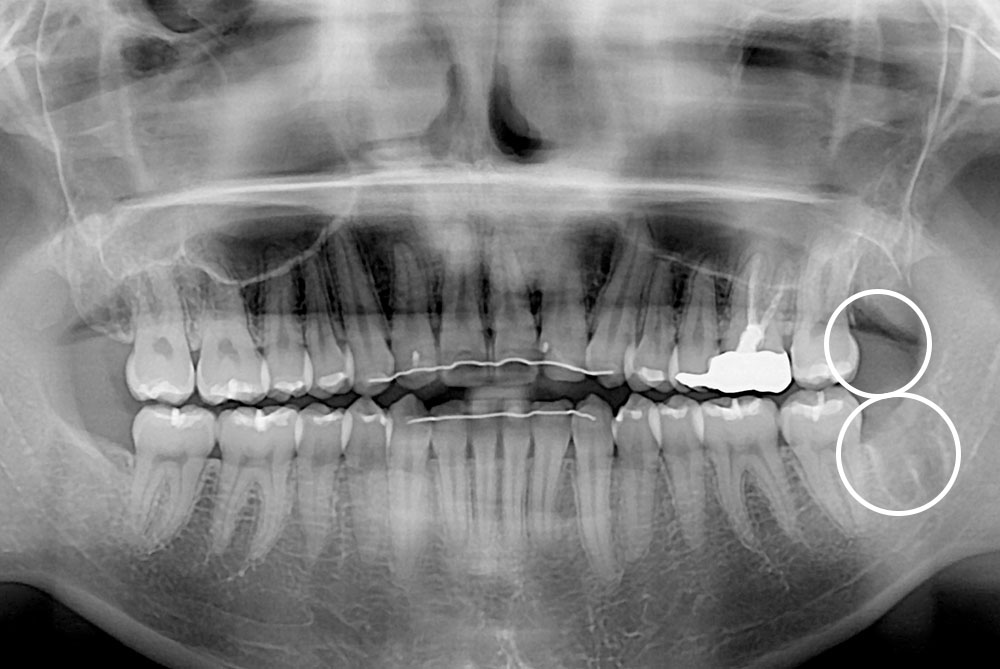

세종치과의 진심 어린 치료는 결과로 말합니다.

실제 내원하신 환자분들의 치료 전·후 사례를 확인해보세요.

모든 치료사례 전후사진은 환자분의 동의하에 촬영되었습니다.

모든사진은 동일 환자분의 전후모습을 촬영하였으며, 사진의 밝기조절 외에 임의 수정이 없음을 알려드립니다.

*수 / 시술 후 개인에 따라 결과의 차이 및 감염 등 부작용이 발생할 수 있으므로 의료진과 충분한 상담 후 결정하시길 바랍니다.